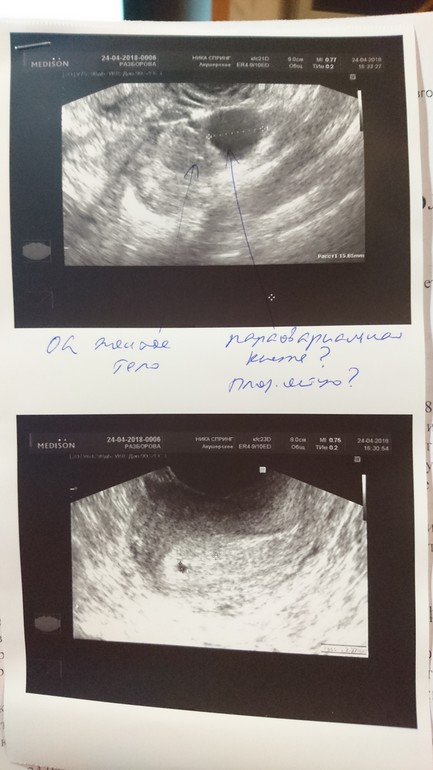

Размер матки 38-34-53, шире нежели при обследованиях ранее (была 38-28-34). М-эхо толщина 11,4мм, эхоструктура изменена за счет анэхогенного округлого включения 2мм на дне, ближе к левому трубному углу. Полость матки не деформирована, жидкостей не обнаружено.

Левый яичник 28-20-22 мм, объем 7,1 куб.см. В структуре желтое тело, рядом или исходит из него анэхогенное округлое образование диаметром 15,8мм, кровоток скудный периферический.

Сказали, что яйцеклетка выходила из левого яичника. Внематочная под вопросом. Отправили на ХГЧ завтра и в пятницу, в субботу на УЗИ.

В общем, как думаете, есть шансы, что вот эта огромная клякса - просто киста, которая решила потеребить мои нервишки?) Я так понимаю, по ХГЧ и повторному УЗИ будет понятно, но я же женщина, я не могу ждать, я хочу зайти на форум и поспрашивать 😊